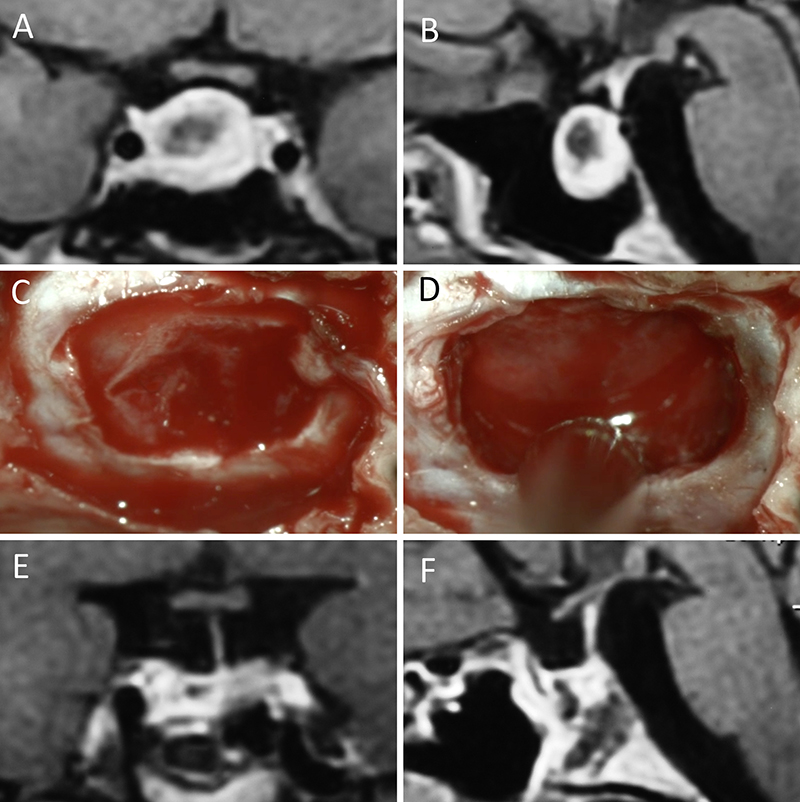

Figura 11: Microadenoma en una mujer de 36 años con Enfermedad de Cushing. Con remisión bioquímica tras la cirugía. A-B: RM preoperatoria; C-D: intraoperatorio; E-F: RM postoperatoria.

Figura 12: Microadenoma en una mujer de 26 años con Enfermedad de Cushing. Con remisión bioquímica tras la cirugía. A-B: RM preoperatoria; C-D: intraoperatorio; E-F: RM postoperatoria.